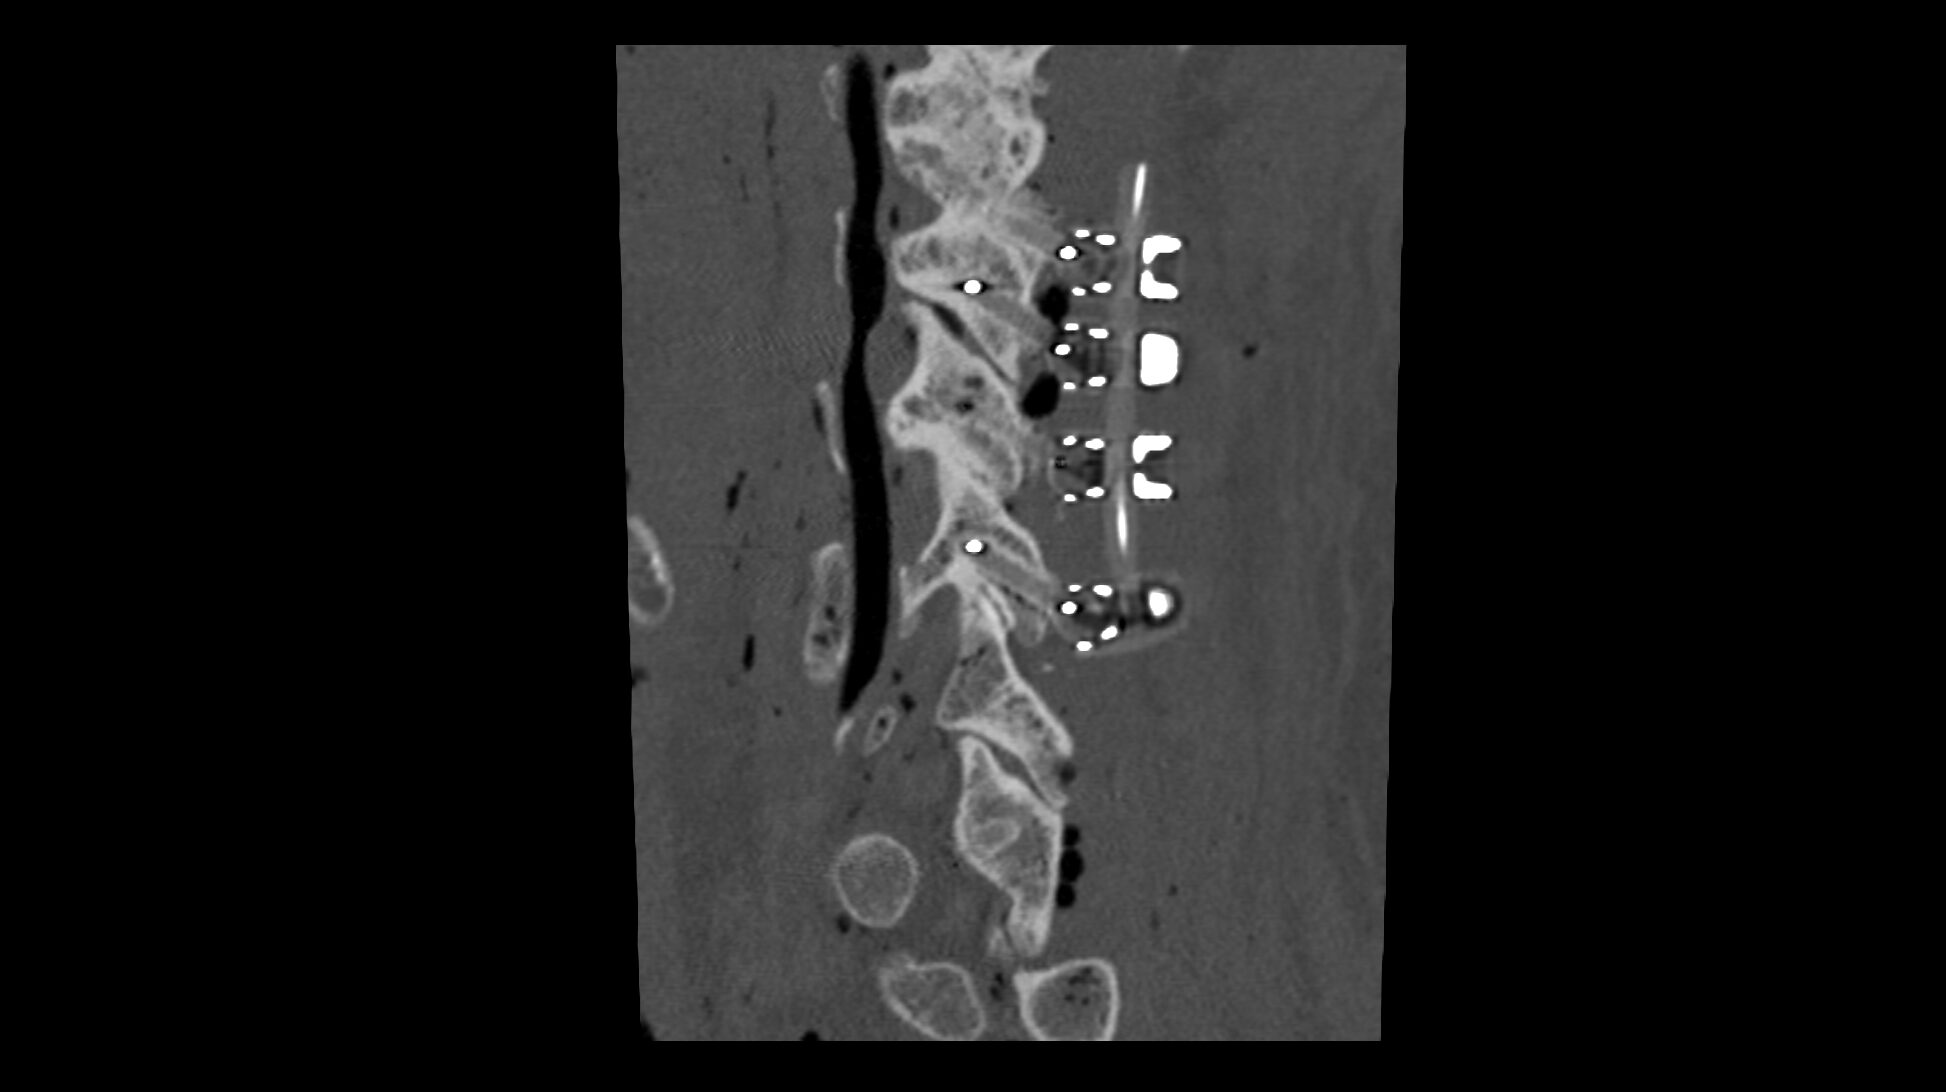

The CMORE® Cervicothoracic (CT) System is an enhanced set of instruments and implants for posterior stabilization of the cervicothoracic spine. The world’s first spinal implants made of nonmetallic and radiolucent BlackArmor® technology now enable a full spectrum of treatment modalities in adjuvant tumor therapy and enhance postoperative imaging diagnostics in the cervicothoracic spine.

Consisting of a full portfolio of polyaxial screws, straight and precontoured rods, axial and parallel connectors, the CMORE® CT System provides the versatility needed to accommodate variations in patients’ anatomy and pathology.

- BlackArmor® material is radiolucent in all diagnostic imaging modes and facilitates adjuvant radiation treatment

- The first tulip made of BlackArmor® material for artifact-free CT and MRI imaging